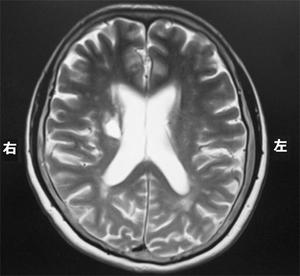

右内包後脚では、左上下肢の運動麻痺が見られるため、この選択肢は正しいです。